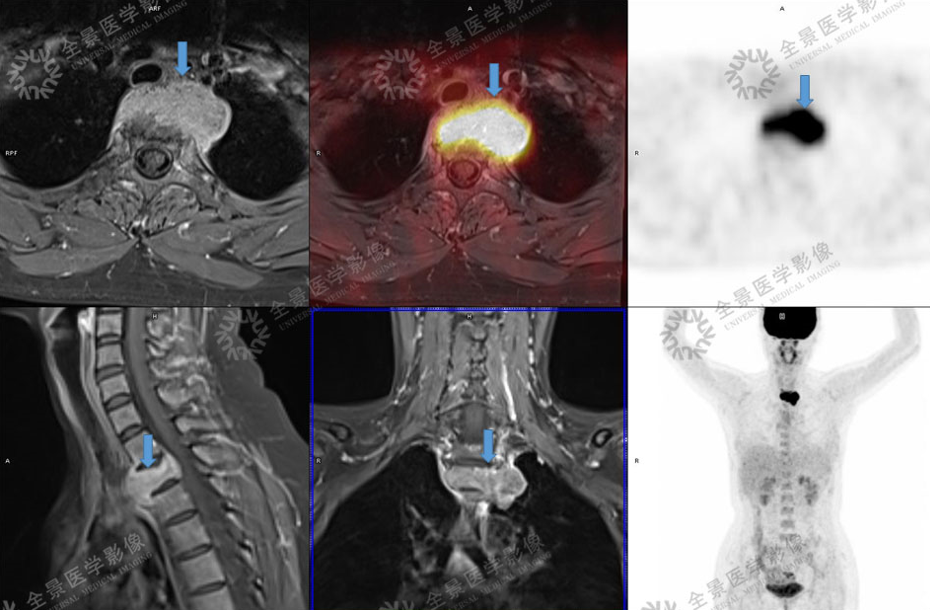

4. 妇科肿瘤

宫颈癌

病灶向上累及子宫峡部,向下累及阴道穹隆及相邻阴道壁,宫颈周围脂肪间隙清晰。

子宫内膜癌

对子宫肌层及周围结构侵犯进行临床分期